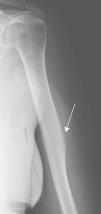

La figura 2 muestra la apariencia típica del pseudoquiste de la cabeza humeral en radiografía simple (flecha). Consiste en un área radiolúcida redondeada en la cabeza humeral debido a una disminución normal de las trabéculas, a menudo asociada con un aumento en el contenido graso5,6. Se localiza en el aspecto superolateral de la cabeza humeral y se identifica en la proyección anteroposterior. Puede haber una fina línea que la delimita en su margen inferior de la médula adyacente y que coincide con el lugar de fusión entre la epífisis y la diáfisis. El resto del margen suele estar mal definido5,7. No es sintomática. En ocasiones plantea el diagnóstico diferencial con lesiones líticas primarias (osteoblastoma, tumor de células gigantes) o secundarias, siendo necesaria la realización de pruebas complementarias (TC o RM).